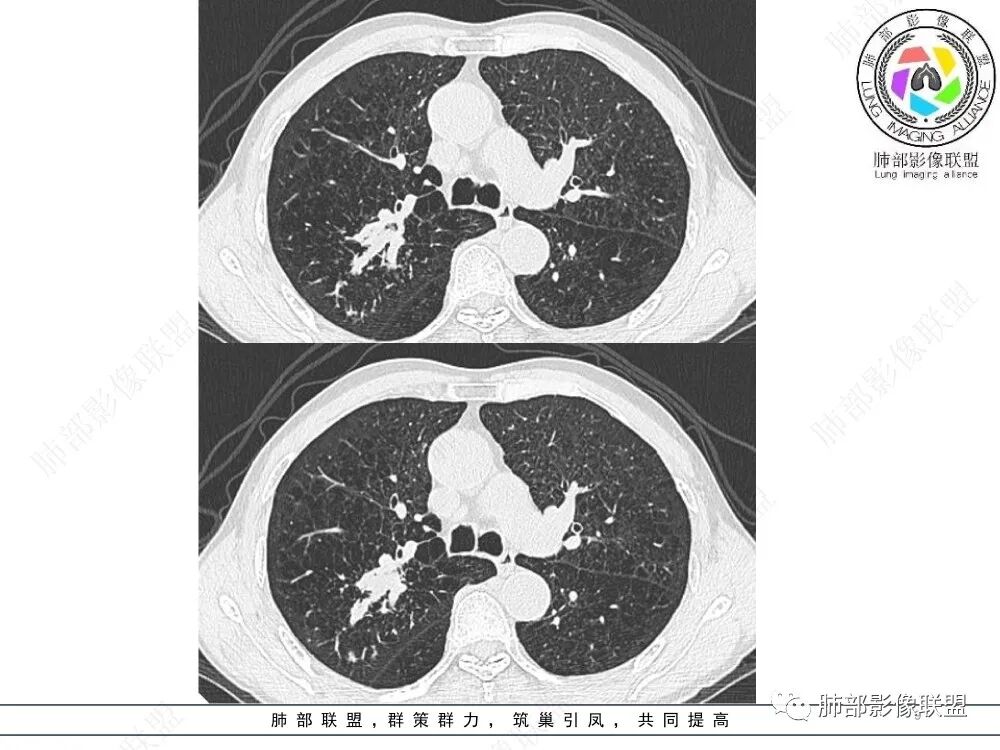

ABPA影像:1、中心型支气管扩张,常常双侧较对称,一般以段、亚段为主,支气管壁增厚,腔内有粘液栓,呈指套状或牙膏状影,粘液栓高密度(约30%),无强化。2、小气道异常∶小叶中心细支气管扩张并充有粘液——树芽征。3、伴随征象∶肺内斑片状、结节状高密度影,呈游走性;扩张支气管远端可伴有阻塞性肺气肿、肺不张,肺纤维化、局部胸膜增厚或积液。4、治疗好转粘液栓消失,扩张支气管的转归∶ 部分不变化,部分较前稍缩小,很少一部分可以恢复正常,一般壁稍增厚。

上图,ABPA,支气管扩张、腔内指套样粘液栓,部分粘液栓呈高密度,较具特征性。

上图,支气管结核。病灶多灶性、多态性。支气管中近端受累,支气管壁增厚不均匀,狭窄后扩张,伴随树芽征、钙化。